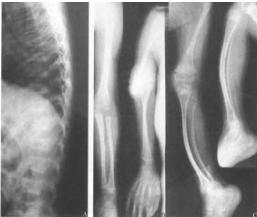

X线表现 可见圆形或卵子圆形的緻密斑点,几乎波及全身,特别是在长骨的骨骺部位及干骺端,但骨干很少有斑点。斑点的大小不一,直径大约由2mm~10mm数目不等。在脊柱、肋骨及锁骨均少见,在颅骨更稀有。骨骼的轮廓改变,骨骺发育亦无影响,关节间隙正常。在成人,斑点一般不再有明显变化,而在儿童则斑点可以增加,消失及融合。 医学百科网 | YxBaike.Com

(3)病灶呈弥漫性多发的密度增大的圆形、椭圆形、圆圈状、结节状阴影,其形态走行,部分与骨的长轴一致。

(4)病灶多累及长骨的两端,密集于干骺端及骨骺,以及骨盆、手、足及不规则骨。越靠近关节病灶越密集,且密度越浓。病灶可相互融合成片而遮盖正常骨组织。 医学百科网 | YxBaike.Com

(5)密度增浓的斑点状病灶的边缘不甚清晰锐利,越靠近中心部位密度越浓,边缘部位密度略淡。

(6)病灶侵及骨的松质骨。骨膜及关节软骨不受侵犯,故关节间隙光整清晰。 医学百科网 | YxBaike.Com

脆弱性骨硬化本病好发于长短管状骨的骨端骨松质内以及肩胛骨、骨盆、腕骨、足骨等扁骨和不规则骨内,很少发生于骨干,在脊柱、肋骨、锁骨、颅骨内极罕见。 医学百科网 | YxBaike.Com

1、X 线检查是发现和诊断本病的主要依据。X 线上病灶呈弥漫多发的圆形、类圆形或融合成条状及团块状致密影,位于骨松质内,走行与骨长轴一致,双侧基本对称,大小在数毫米至2 cm 之间;越靠近关节病灶越密集密度也越高;绝大多数病灶中心密度高边缘密度低,也有少数病灶中心密度偏低,但其边缘均较清楚;病灶不侵犯骨膜及关节软骨,关节间隙清晰。

2、CT 能更清晰地显示病灶的部位、大小、形状及与骨皮质的关系,还能发现X 线平片难以显示的微小病灶。CT 表现为病灶位于骨松质内,并与骨小梁分布一致,少数位于骨皮质内或骨皮质下,相应部位骨皮质增厚密度增高。多呈圆形或卵圆形高密度结节影,边界清楚,有的呈团块状改变。 医学百科网 | YxBaike.Com

3、MR 表现为病灶多发不均匀散布于骨松质内,呈圆形、类圆形结节及不规则条状异常信号,在T1WI 与T2WI 上均为极低信号,边界清楚,多发病灶聚集成“蜂窝状”,周围软组织无异常信号。 医学百科网 | YxBaike.Com